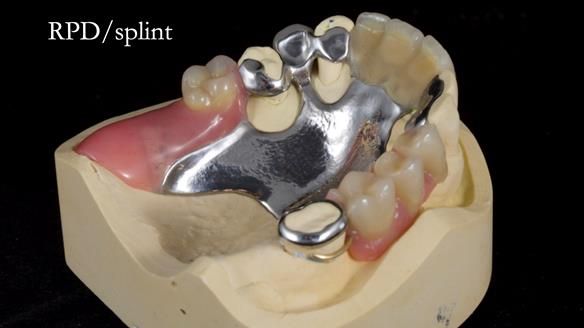

This edition features the case of Edgar, who sought help for a poorly fitting, acrylic-based partial denture that rocked, affected his speech, and caused discomfort. After considering various treatment options, including dental implants, Edgar opted for a metal-based removable partial denture, designed by myself with input from my technician, Rowan Garstang.

Treatment Process: I provided the clinical work while Rowan Garstang delivered the technical aspects. The treatment required fifteen visits to fit and review Edgar.